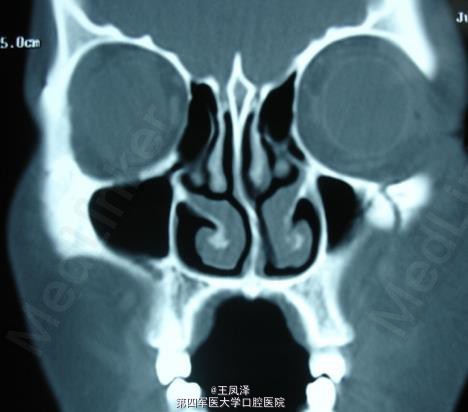

颧骨-眶底骨折病历

患者,女,25岁,车祸后送诊

双侧上颌骨骨折、左颧骨骨折

眶底骨折缺损重建